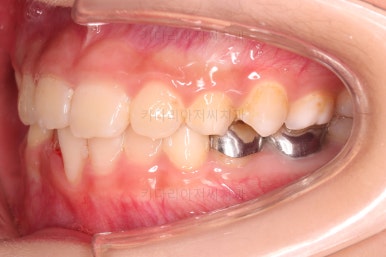

바로 부산어린이교정 전후사진 비교해 볼게요.

단, 2주만에 문제시 되는 딱 한 개의 치아에만 포커스를 맞춰 해당 치아 반대교합만 개선해준 매우 훌륭한 치료였습니다.

이상 매우 간단한 장치로 매우 빠르게 반대교합을 치료한 부산어린이교정 두 명의 치료사례였습니다.